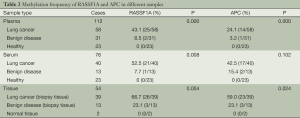

Methylation frequency of RASSF1A and APC

Methylation status of RASSF1A and APC for 89 patients as well as 23 normal samples was examined using QMSP. Representative results of methylation analysis by QMSP were shown in Figure 2, and detailed data regarding the frequency of aberrant methylation were summarized in Table 2.

Full table

For RASSF1A, the methylation rate of three different sample types (plasma, serum and tissue) all showed significant differences among three groups. Significant differences for APC were observed in plasma and tissues. However, the benign disease group showed a relatively lower methylation frequency. No methylation for both of the two genes was found in the healthy group. The difference between benign disease group and healthy group was not significant. Besides, the smoking rates of caner group and benign group were both around 60%.

Combination methylation results

Considering the condition of at least one gene methylation of RASSF1A and APC, we got a much higher methylation frequency list in Table 4. For lung cancer patients, we combined three kinds of samples as well as two genes all together and the methylation rate was 88.5%. Among the 26 early stage lung cancer patients, only three patients showed no methylation for both RASSF1A and APC in three different sample types (Figure 4). The coincidence rate of methylation between plasma and serum of the 26 early stage lung cancer patients was 65.4% for RASSF1A and 73.1% for APC. For RASSF1A and APC, the methylation comparation between plasma and biopsy tissue samples both showed a coincidence rate of 57.7%. The coincidence rate between serum and biopsy tissue samples was 65.4% with RASSF1A and 57.7% with APC. As for RASSF1A, twelve patients’ methylation status of biopsy tissue matched the plasma and serum and the coincidence rate attains 46.2%. It displayed the same as for APC. There were eight patients’ positive methylation results in blood did not match their biopsy tissue results for RASSF1A. And for APC, the number is six. Also, three patients’ positive biopsy tissue methylation results did not match their blood's detection results for RASSF1A. And for APC, there were four cases.

As listed in Table 5, the methylation rates of RASSF1A and APC of paired biopsy tissue, plasma and serum samples were all more than 50%. Data analysis revealed that the differences were not significant.